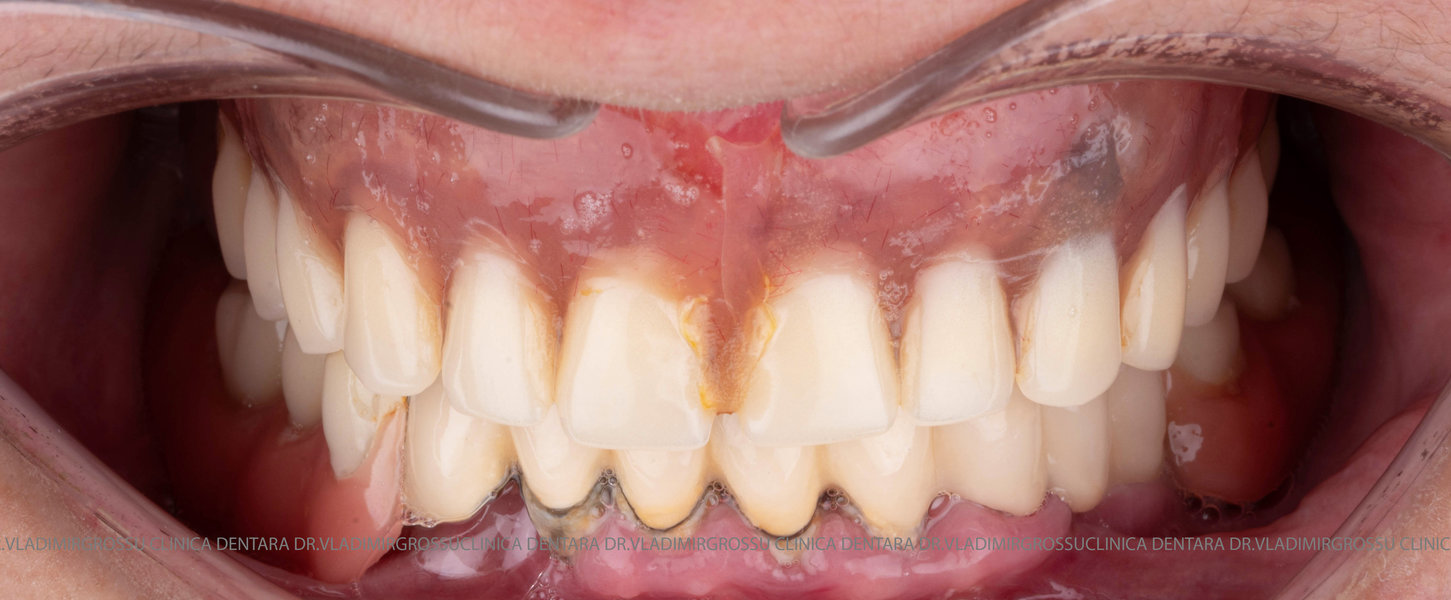

Tomografii (CBCT)

Caz 2